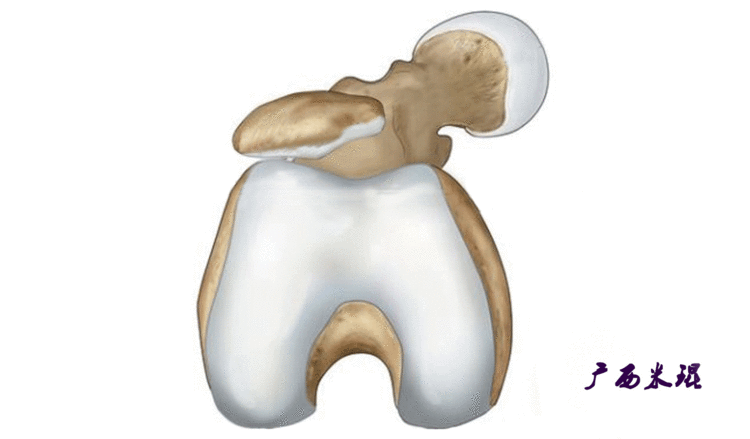

说到髌骨脱位,首先就要了解髌骨,髌骨是人体最大的籽骨,倒三角状位于膝关节前方,它的上缘与股四头肌腱相连,下缘通过髌韧带止于胫骨结节上,两侧为股四头肌扩张部,髌骨后方的凸面为光滑的关节面,与股骨下端内外髁之间的滑车凹面关节面形成关节。尽管股四头肌中的股直肌、股中间肌、股外侧肌的作用方向与髌韧带不在一条直线上,髌骨有向外突出的倾向,但因股内侧肌有向内上方牵拉作用力而使髌骨维持在正常位置。

以欧洲为代表的学者认为滑车发育不良是复发性髌骨脱位的根本因素,因此通过加深股骨滑车间沟纠正髌骨脱位的滑车成形术成为这个学派的主要治疗方法,但滑车成形术更不是万能的,它无法解决髌骨脱位的其他很多致病因素,在某些病例,滑车成形加上MPFL重建可能是不错的选择。